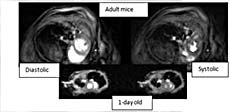

MRI can also be used to image the beating heart in live mice. The images shown here are of different phases of the cardiac cycle for an adult and a 1-day old mouse.

Understanding location and severity of a brain lesion and its response to therapy is one application where MRI is advantageous.

Here we use MRI to study development of the traumatic injured area over time.